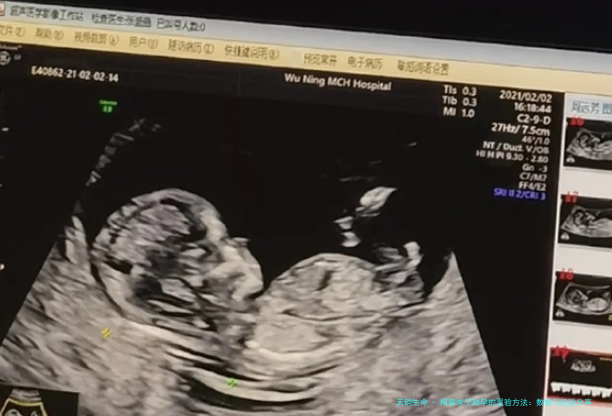

说到医疗方法,试管婴儿(IVF)绝对是热门选项。近年来,IVF的成功率提高了不少,尤其是对于35岁以下的女性,成功率能超过60%。但别忘了,这过程可能挺折腾的——激素注射、多次检查,还有不小的经济压力。我有个朋友,去年通过IVF成功怀上了双胞胎,她分享说:“关键是找到靠谱的医院和医生,别光看广告,得多咨询。”此外,药物促排卵和人工授精也是常见选项,数据表明它们的成功率在20%-30%之间,适合轻度不孕 cases。被动句来说,这些方法往往被优先考虑,但当结合生活方式调整时,效果会倍增。